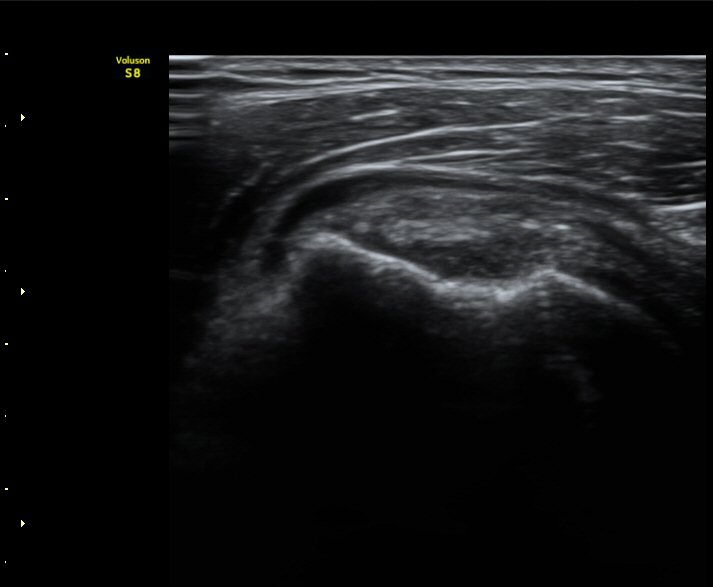

3°³¿ù ÈÄ ÃßÀû°Ë»ç

2049205267_d4912430_US181205109.jpg